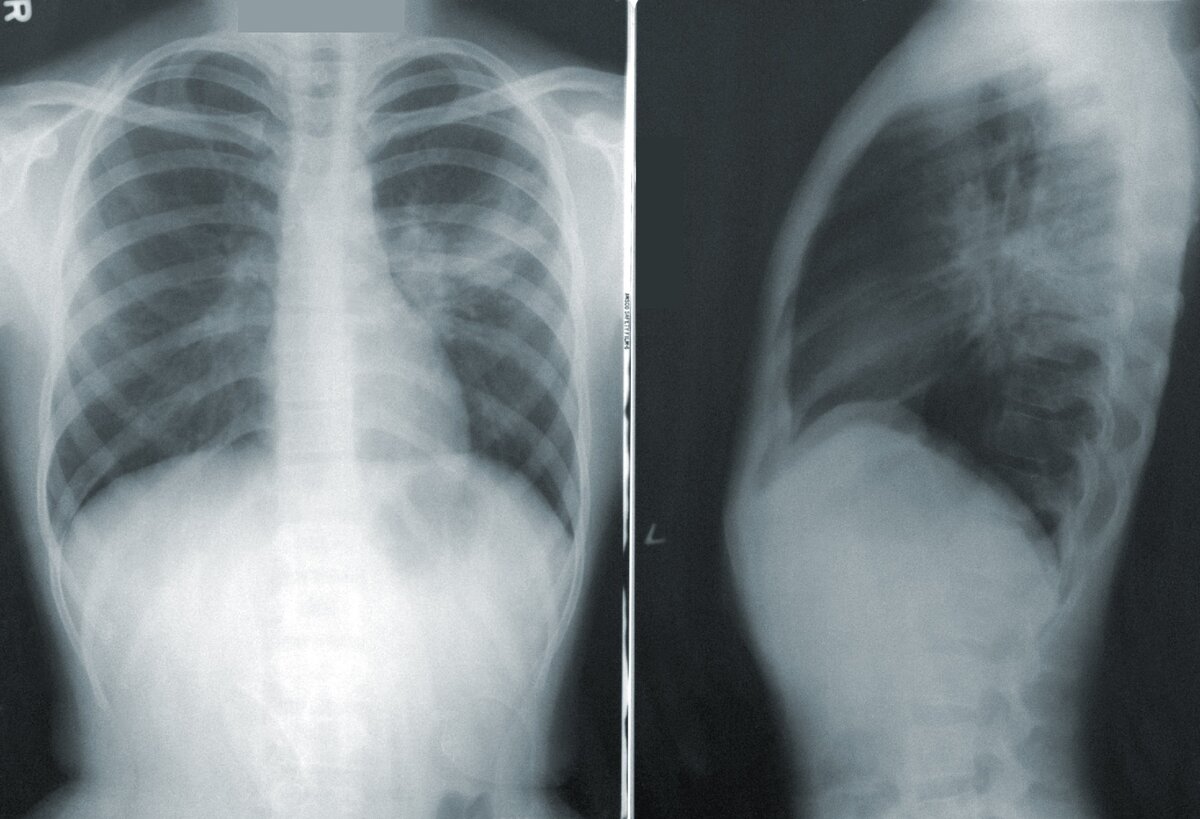

Пневмония - это довольно серьезное заболевание. А это значит, что лечить его самостоятельно ни в коем случае нельзя. Прежде всего нужно обратиться к квалифицированным специалистам, в больницу. Далее нужно будет сдать кровь на анализы и пройти рентген легких. Эти действия помогут определить форму и вид заболевания, будут назначены соответствующее лечение и

Пневмония - это довольно серьезное заболевание. А это значит, что лечить его самостоятельно ни в коем случае нельзя. Прежде всего нужно обратиться к квалифицированным специалистам, в больницу. Далее нужно будет сдать кровь на анализы и пройти рентген легких. Эти действия помогут определить форму и вид заболевания, будут назначены соответствующее лечение и антибактериальные препараты.